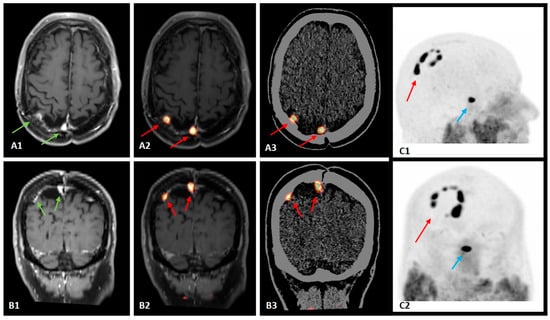

“Rosary Sign” at Somatostatin Receptor PET in a Case of Recurrent Meningioma